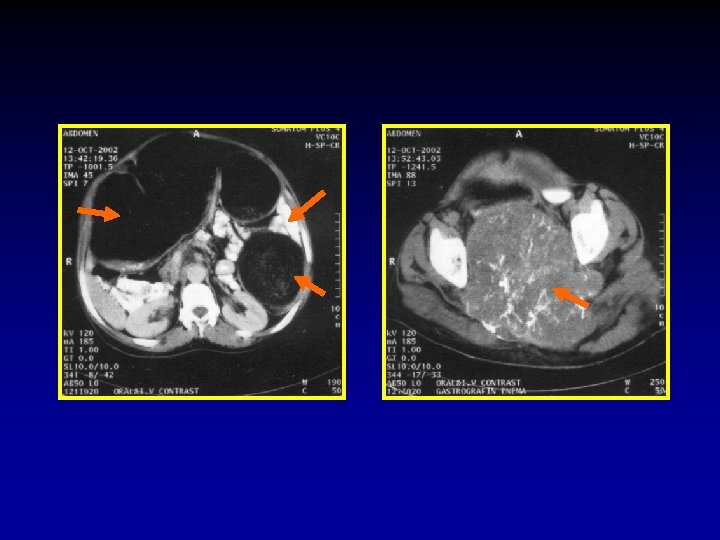

The CT signs of closed loop obstruction of the small intestine are: 1. Evidence of small bowel obstruction. 2. A U-Shaped or radial configuration of the fluid filled dilated loops. 3. At the site of obstruction, a whirl sign, beak sign, triangular loop, or two adjacent collapsed loops.

A At U-Shaped the site Evidence of configuration obstruction of. The small Whirl of two bowel theadjacent sign fluid obstruction. filled collapsed dilatedloops